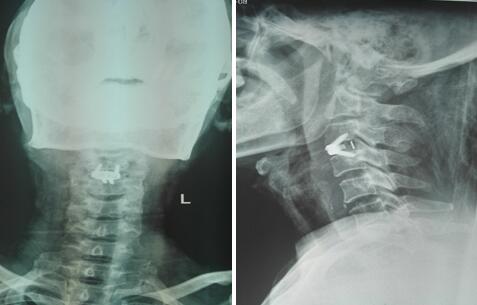

术后颈椎正侧位X线片